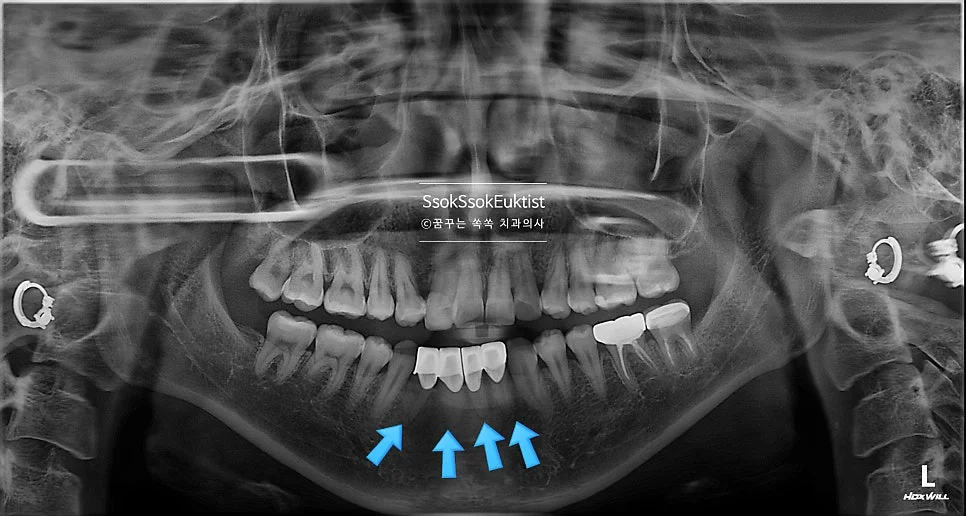

파노라마 X-ray — 아래 앞니 4개 크라운 부위 (화살표)